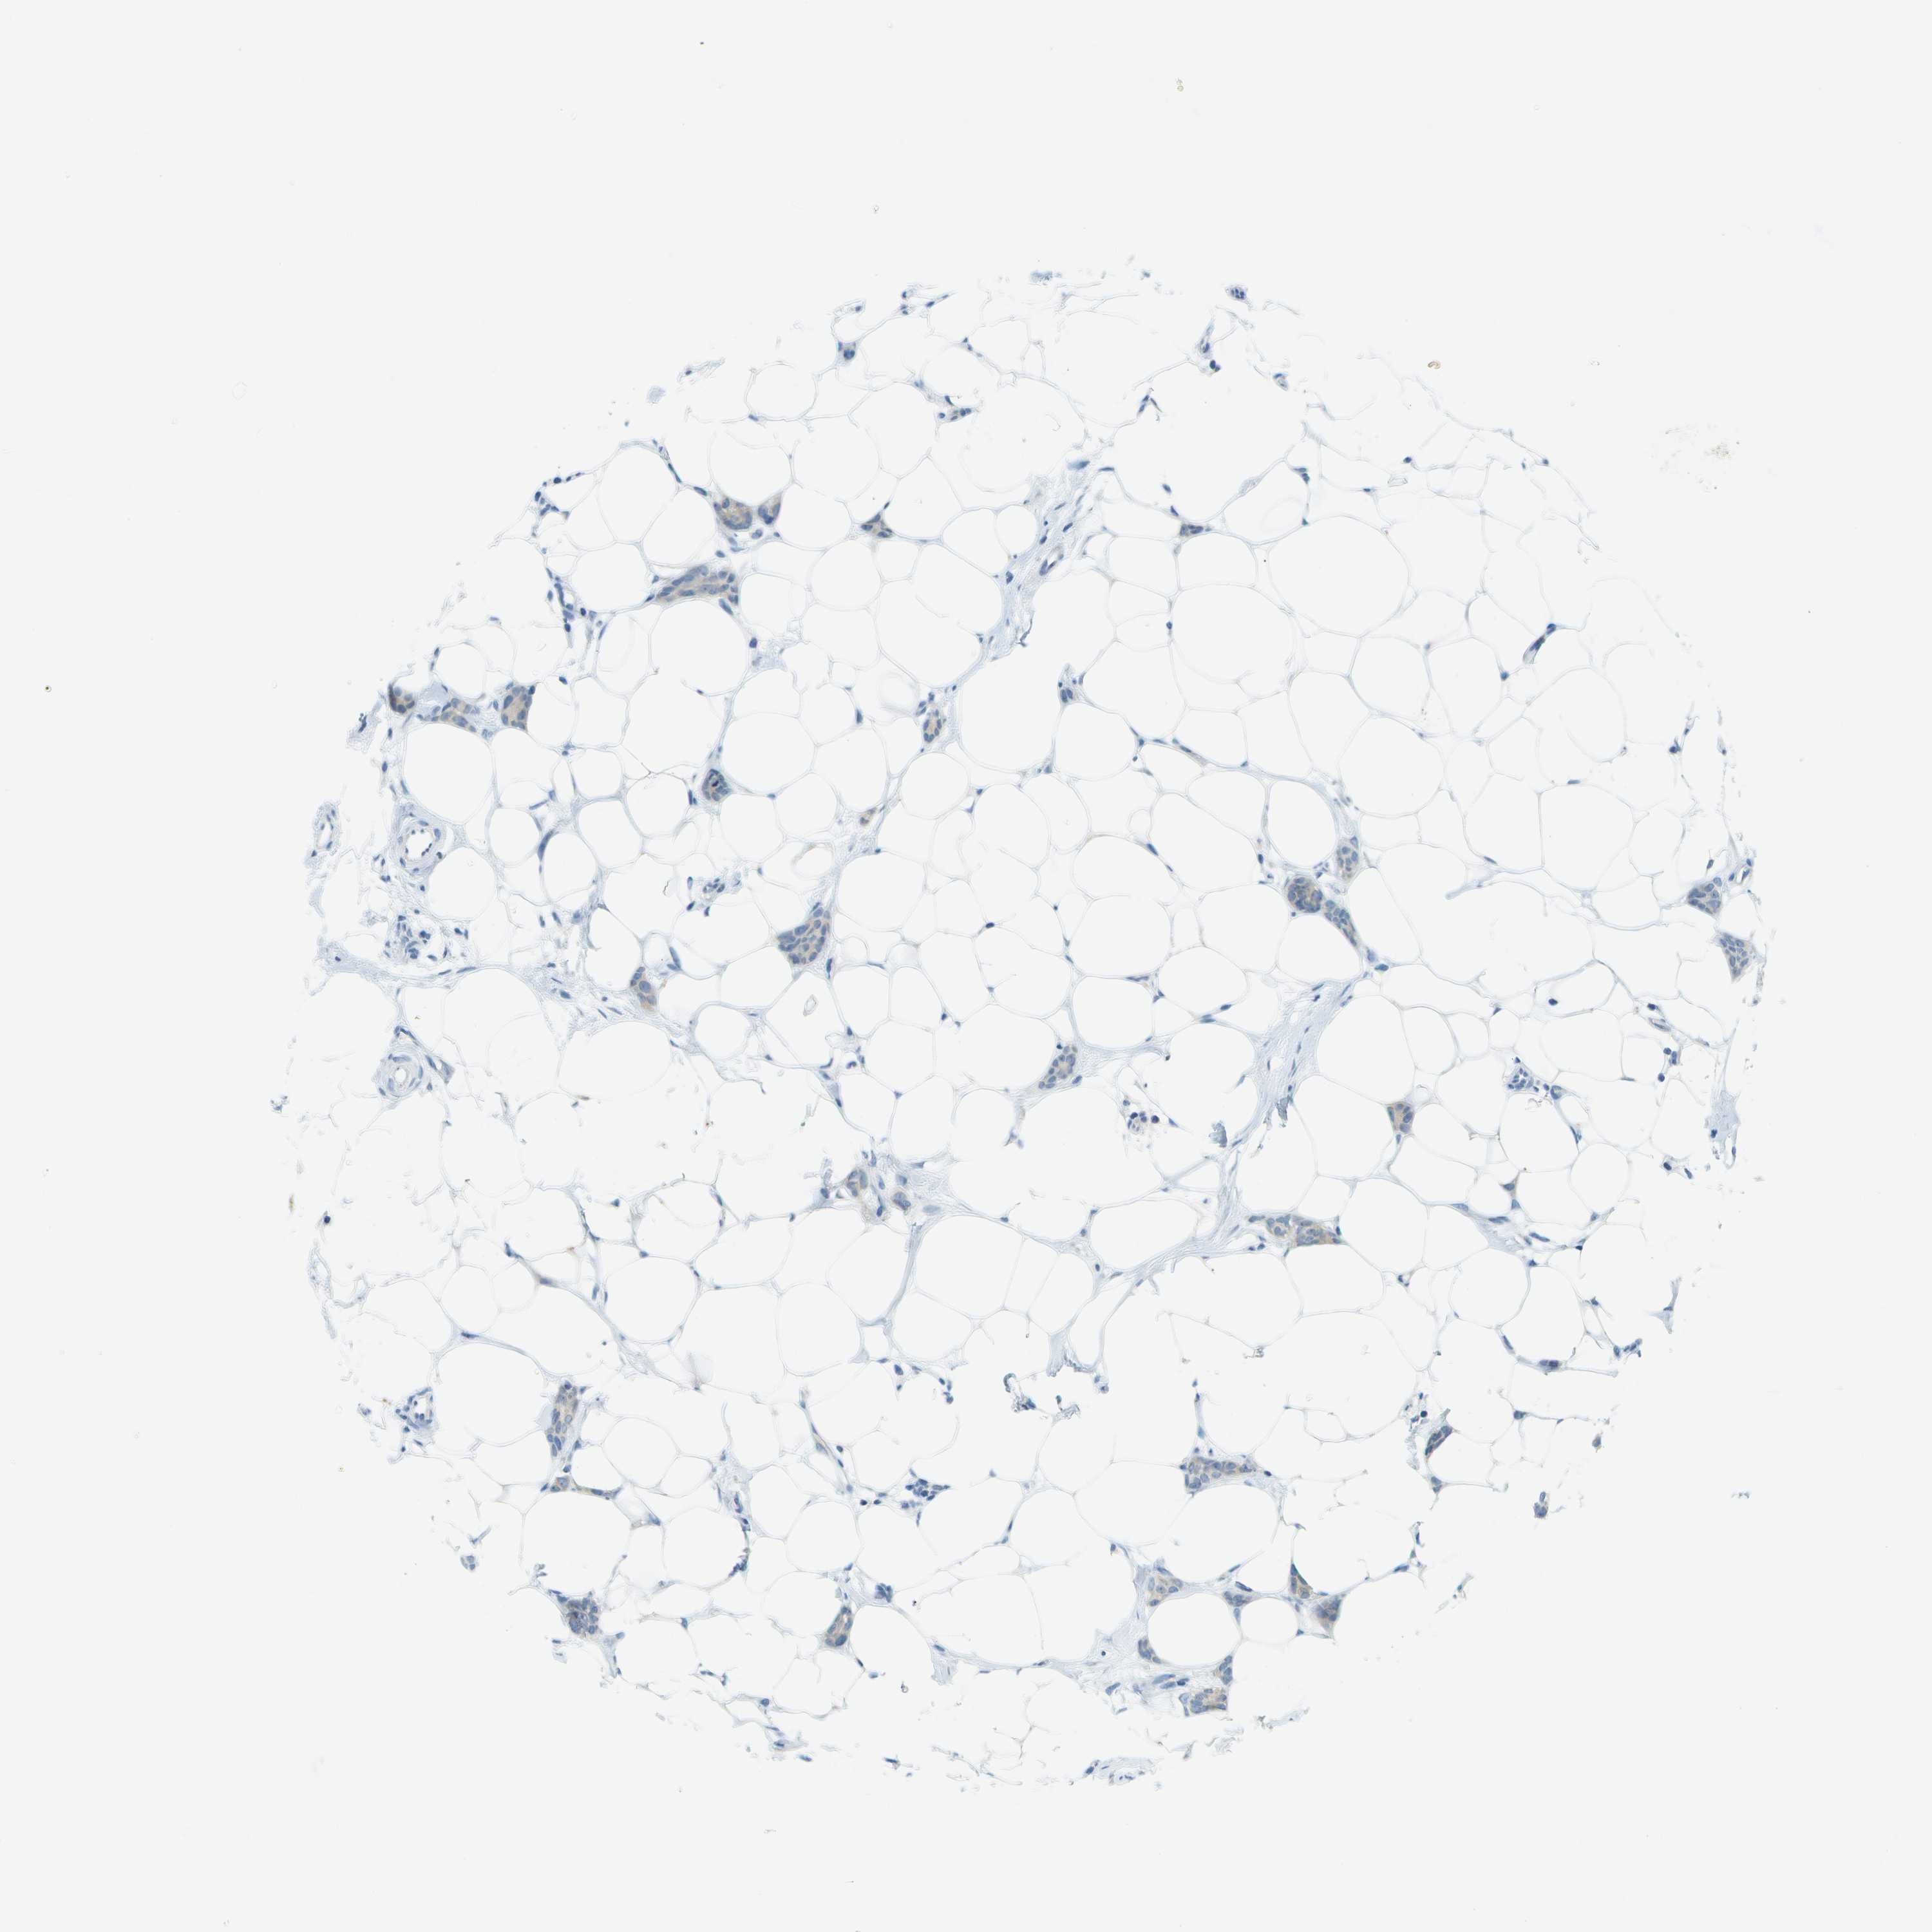

CANCER BREAST CANCER Show tissue menu

BRCA TCGA BRCA VALIDATION PROTEIN EXPRESSION

Breast cancer

Human cancer